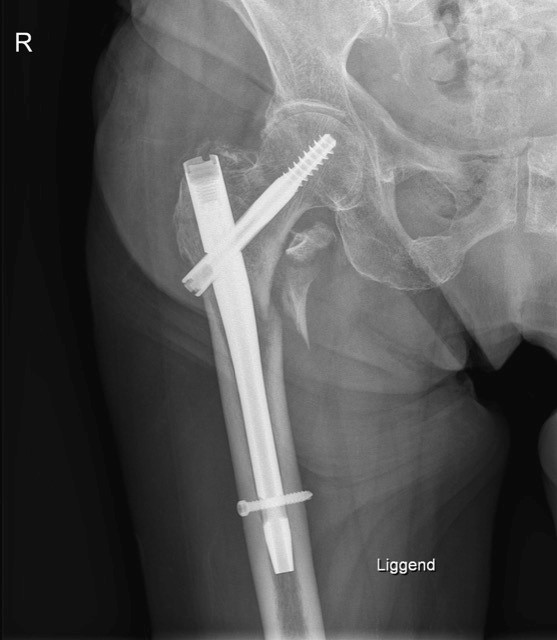

- Gammangel

- Bij lage heupfracturen (onder het gewrichtskapsel in tussen beide trochatners)

- Zowel oude als jonge populatie

- Onmiddelijke steunname